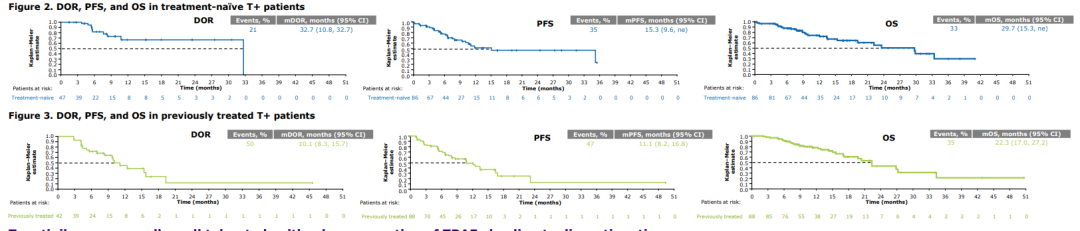

特泊替尼在MET 14外显子跳跃突变非小细胞肺癌中的疗效和安全性:VI...

特泊替尼在MET 14外显子跳跃突变非小细胞肺癌中的疗效和安全性:VI...